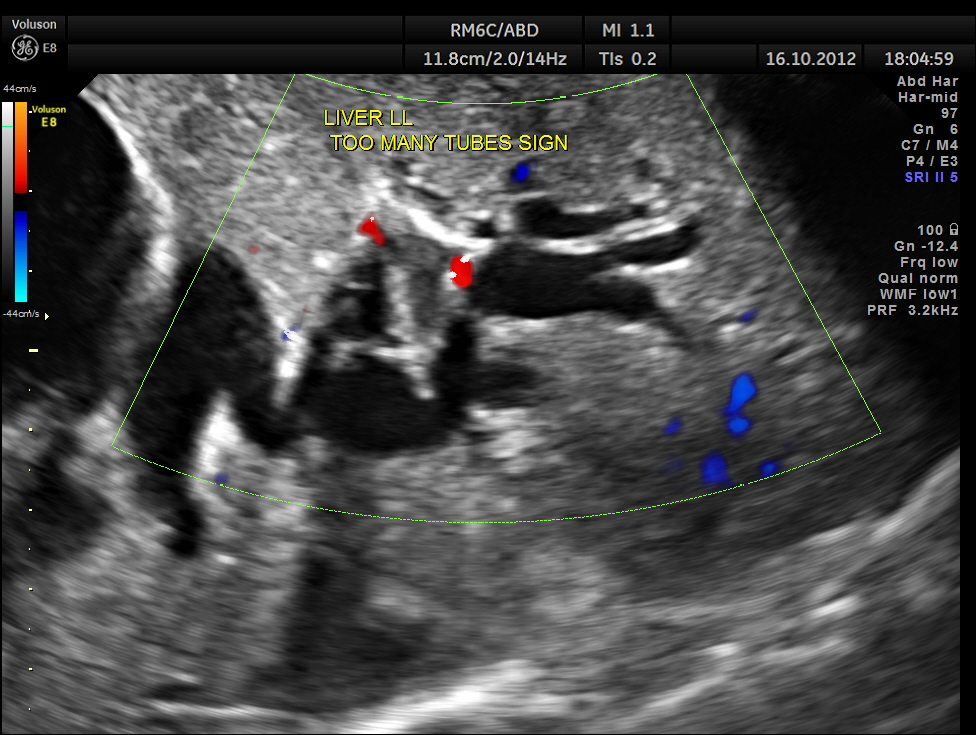

Courvoisier’s law (or Courvoisier syndrome, or Courvoisier’s sign or Courvoisier-Terrier’s sign) states that in the presence of an enlarged gallbladder which is nontender and accompanied with mild jaundice, the cause is unlikely to be gallstones. Usually, the term is used to describe the physical examination finding of the right-upper quadrant of the abdomen. This sign implicated possible malignancy of the gall bladder or pancreas and the swelling is unlikely due to gallstones.

This was a 55 year old man with history of jaundice and upper abdominal pain .